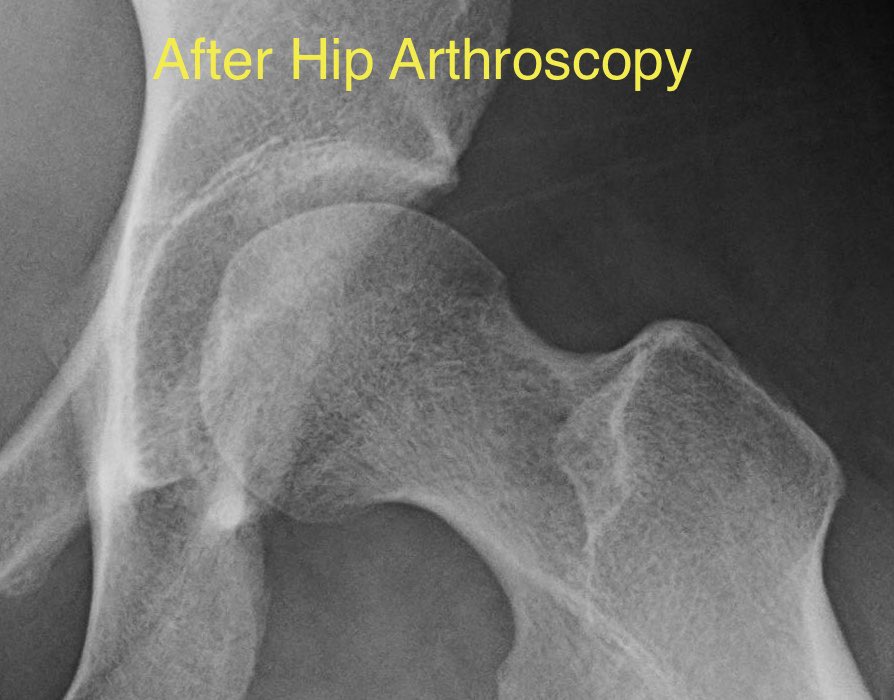

Here’s the same hip after a hip scope.